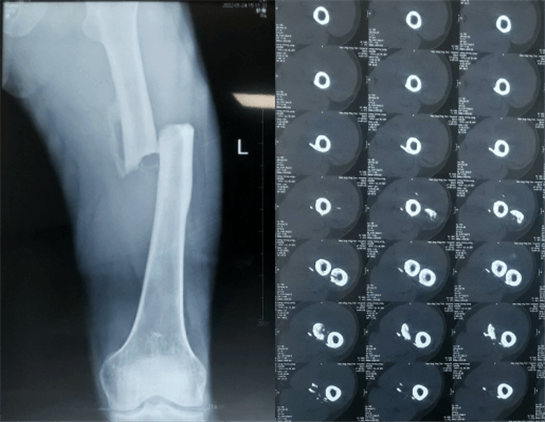

患者:男性,43岁,左股骨干骨折髓内钉内固定术

股骨是下肢的主要负重骨,有其特殊的解剖关系,周围肌肉发达,因此一旦股骨干骨折后如果治疗不当,容易造成肌肉牵拉,导致畸形和功能障碍。治疗股骨干骨折,必须遵循恢复肢体的长度及力线,无旋转,尽量行以微创,?;す钦劬植垦耍俳?。髓内钉对骨折的固定能够达到较大的稳定性和坚固性,可以减少医源性污染,减少软组织分离及周围血供破坏,有利于骨折早期愈合,是治疗股骨干骨折的首要治疗方法。

术前检查